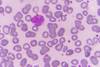

Lymphocyte

Most are small; a bit bigger than RBCs, about 6-9µm in diameter. The rest (around 10%) are larger, about 10-14µm in diameter. These larger cells have more cytoplasm, more free ribosomes and mitochondria.

Lymphocytes can look like monocytes, except that lymphocytes do not have a kidney-bean shaped shaped nucleus, and are usually smaller. Larger lymphocytes are commonly activated lymphocytes.

They have a small spherical nucleus and has abundant dark staining condensed chromatin. Not much cytoplasm can be seen, and it is basophilic (pale blue/purple staining).

These are the second most common WBC (20-50%), and are easy to find in blood smears.

Although the cells look similar there are two main types, B-cells and T-cells.

B-cells develop in the bone marrow. T cells are born in the bone marrow, but are matured in the Thymus.

Function:

The B-cells develop into plasma cells which make antibodies, The T-cells attack viruses, cancer cells, and transplants.